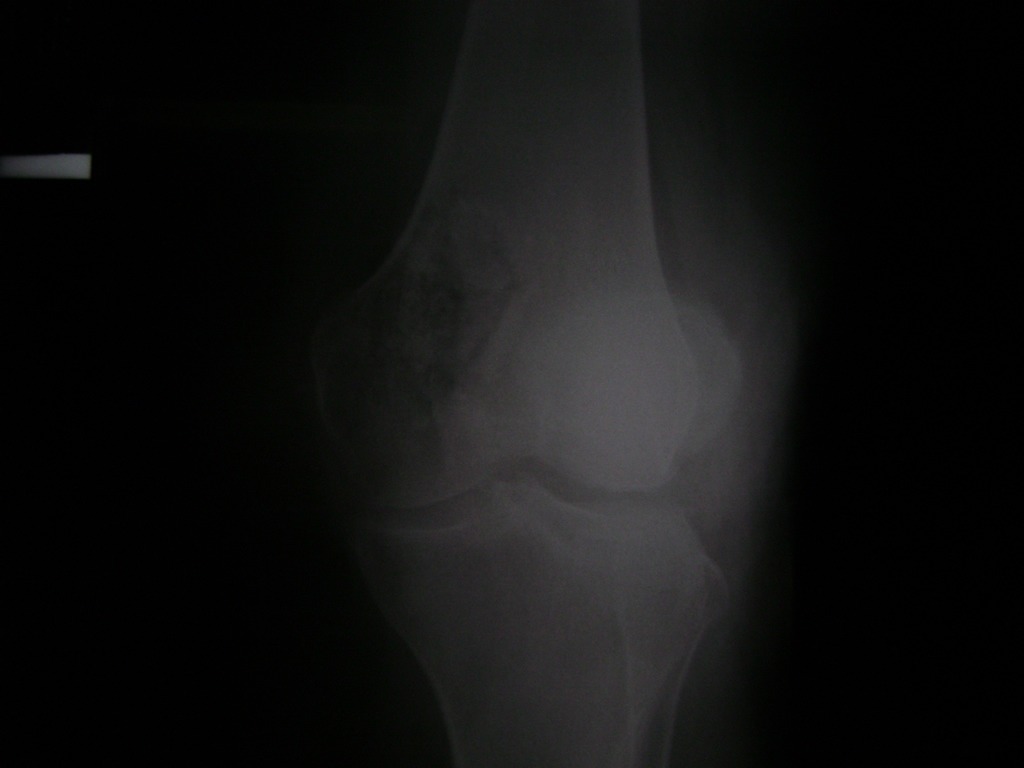

Fémur - Rodilla

La artroscopia de rodilla es un cirugía en el cual la estructura interna de la articulación es examinada ya sea para realizar un diagnostico o para realizar un tratamiento, este procedimiento se realiza utilizando un instrumento parecido a un pequeño tubo llamado artroscopio.